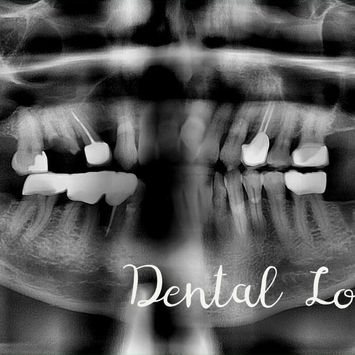

Pre-operative CBCT confirms:

3-rooted #16 with extensive caries.

#46: prior crowning with distal cervical radiolucency—KIV recurrent caries/leakage.

#17 (MO): AR with possible leakage—KIV crowning.

Pre-operative CBCT taken.

Adjacent structures assessed—maxillary sinus evaluated for proximity.

Post-op CBCT taken.

No retained fragments noted.

Maxillary sinus not involved.

Adjacent teeth unaffected.